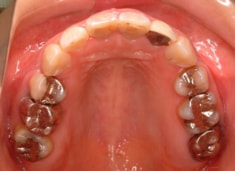

治療前